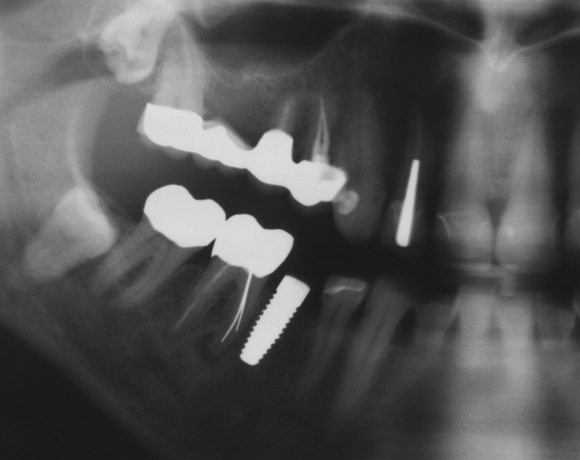

Ein Projekt aus dem Jahr 2013

Bei diesem Patientenfall wird die offene Abdrucknahme gezeigt und die Herstellung einer Krone auf einen CAD/CAM Pfosten.